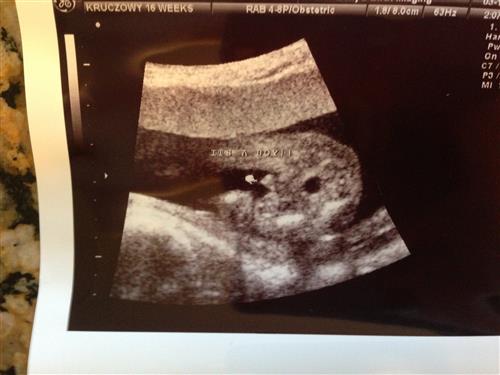

16 Week Gender Guess w/ pic

So I went for a private gender ultrasound today at 16 weeks and she guessed that its 80% likely to be a boy.

We have one DS at home and this pregnancy has been totally different so we were surprised to hear that. I read that sometimes they can mistake a tailbone for a boy part.

That certainly looks like a boy!! I have three of them, this is what the scans basically looked like, lol!

It that isn't a boy i'd be very surprised. Congrats!!! Brothers are awesome :)

Looks like a boy. I'm pregnant with my third. My pregnancies have been different.

That looks like a boy for sure!

Boy!

Looks like a boy to me.